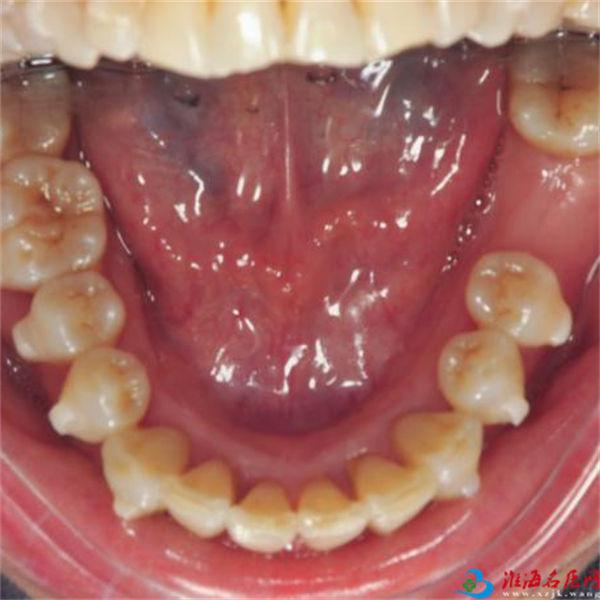

矫正前

矫正后